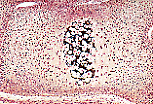

Les os